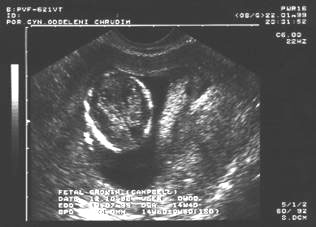

10. týden: dvojvaječná dvojčata

10.týden